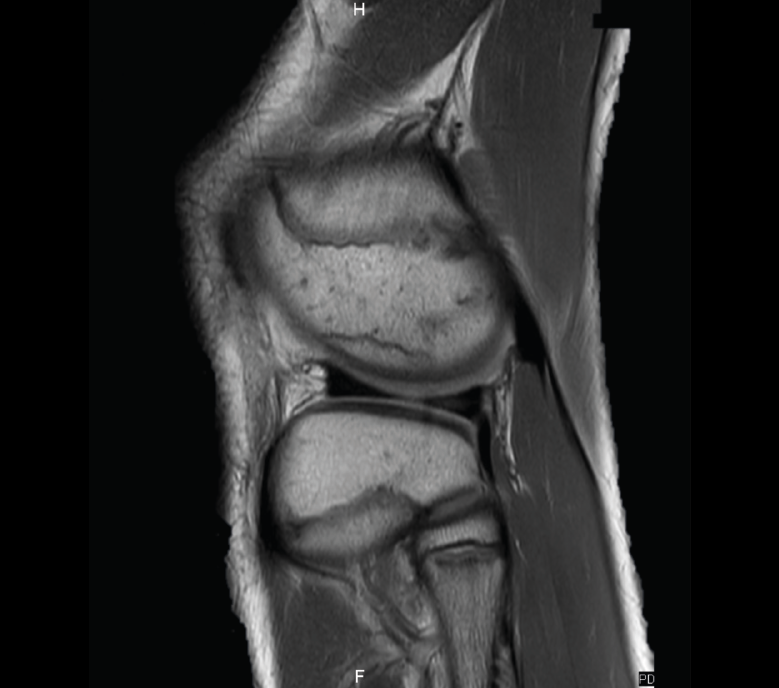

Los infartos medulares óseos aparecen en el 0,06% de los pacientes a quienes se les ha realizado una RM del aparato locomotor. Se presentan como lesiones segmentarias, puramente medulares, sin afección cortical, normalmente múltiples y que afectan predominantemente a los huesos largos de las extremidades, sobre todo las inferiores. La RM es esencial en el diagnóstico por imagen, apareciendo como lesiones óseas intramedulares de contornos serpiginosos hipo- o isointensos en secuencias T1 e hiperintensos en T2. Por tanto, la RM es el instrumento crucial en las fases iniciales, ya que permite caracterizar las lesiones y proceder a su diagnóstico temprano(19)(Figura 52).

Figura 52. A: corte de secuencia coronal T2 Fat-Sat con infartos óseos en el fémur y la tibia; B: corte de secuencia sagital T1 con infartos óseos en el fémur y la tibia.